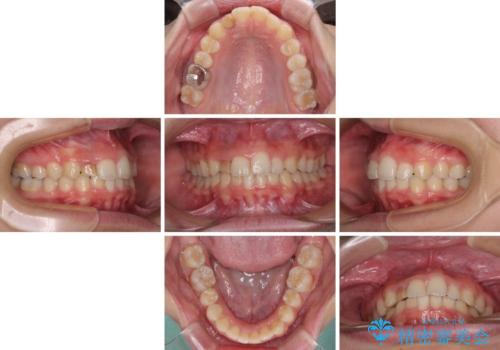

- 前歯の歯並びと不自然な色をした前歯のクラウンを気にして来院された患者様です。

上下前歯の歯列不正はインビザラインにより歯列を整え、その後に、前歯をオーダーメイドタイプのオールセラミッククラウンにて補綴治療することとしました。

前歯のデコボコを一番気にしていらっしゃいましたが、矯正治療により下顎前歯が隠れるほどのディープバイトも一緒に改善され、奥歯に負担のかかりにくい咬み合わせとなりました。